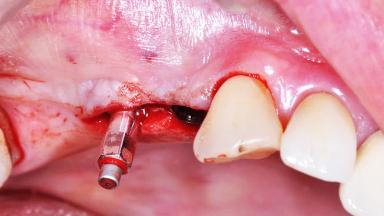

Implant Placement with Simultaneous Sinus Floor Elevation (Lateral Window Technique)

Surgical treatment of a 68-year-old female patient who experienced failure of her conventional bridge in the right maxilla. After removal of the compromised abutment teeth and a healing period of 6 weeks, a sinus floor elevation procedure using the lateral window technique and a composite graft to correct the insufficient bone height is carried out.

Two dental implants are placed in the same surgical session. The case concludes with the presentation of the final fixed dental prosthesis with a distal cantilever unit.